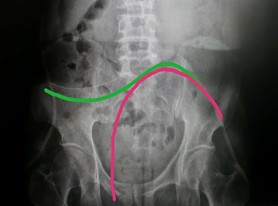

红色的线条是腹透管良好的位置,绿色的是腹透管位置偏高。

a. 腹透导管位置较高或漂管:站立灌入腹透液、适当活动上下楼梯、灌肠通便、变换体位;